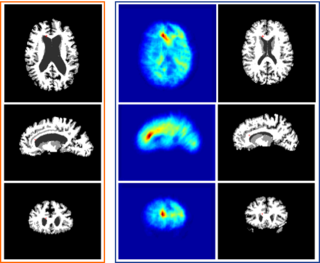

Results from the new implementation are:

One WML Segmentation side:

- Skull stripping is being developed. For WML segmentation, skull stripping is not THE most critical piece. The accuracy requirement is relaxed.

- Support vector machine classification will be using/extending SVMShapeAnalysis in Namic Sandbox developed by MIT group.